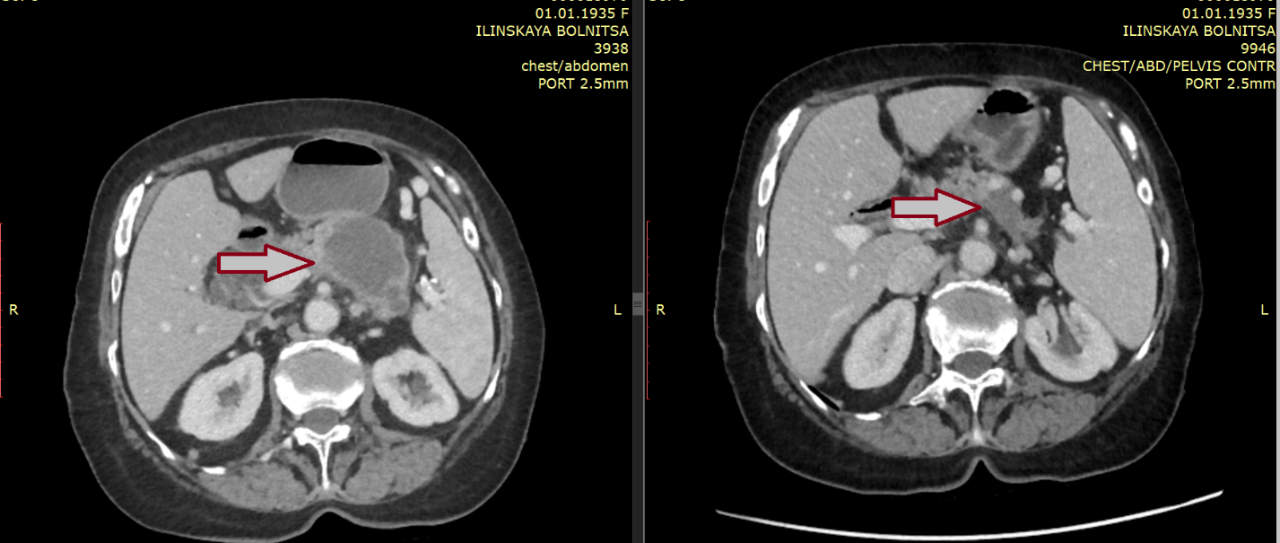

С февраля 2021 г. начата 2-я линия химиотерапии по схеме CapeOx. В мае 2021 г. было достигнуто уменьшение измеримых очагов опухоли на 55%.

В дальнейшем, учитывая неудовлетворительную переносимость и токсичность на фоне лечения, терапия была скорректирована и проводилась по менее интенсивному протоколу лечения (de Gramont, химиотерапия только одним препаратом 5-фторурацилом с интервалом в каждые 14 дней). При проведении дальнейших курсов химиотерапии качество жизни улучшилось, а эффективность удалось сохранить — так, при последующих контрольных обследованиях подтверждалось сохранение достигнутого эффекта лечения, а онкомаркер СА 19-9 и вовсе нормализовался (за период лечения 2849 -> 9 ед/мл).

Суммарно до сентября 2022 г. проведено 23 курса химиотерапии 2-й линии. В дальнейшем пациентке было рекомендовано динамическое наблюдение — выполнение контрольных обследований (КТ органов грудной клетки, органов брюшной полости и малого таза с в/в контрастированием и оценка динамики CA 19-9) каждые 3-6 месяцев, и по данным последнего обследования данных за прогрессирование не получено.